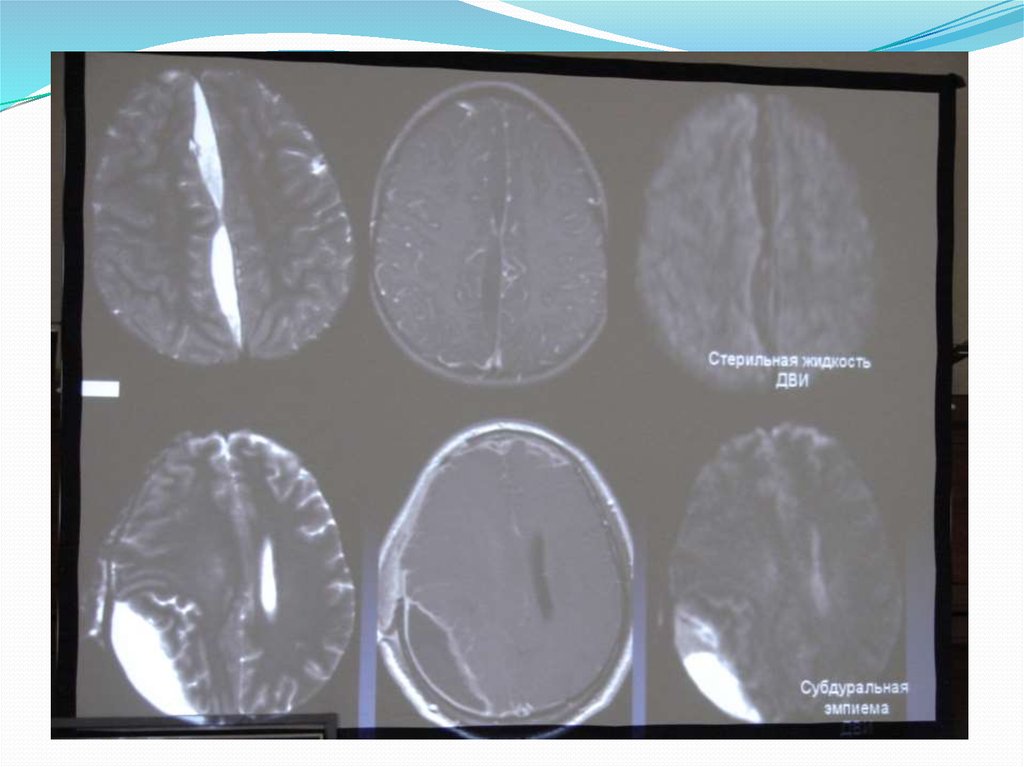

9. МЕНИНГИТ

При подозрении – МРТ с контрастным усилением.

Существует два патоморфологических типа:

Лептоменингит–выраженное усиление

арахноидальной оболочки.

Дура-субарахноидальный – усиление ТМО.